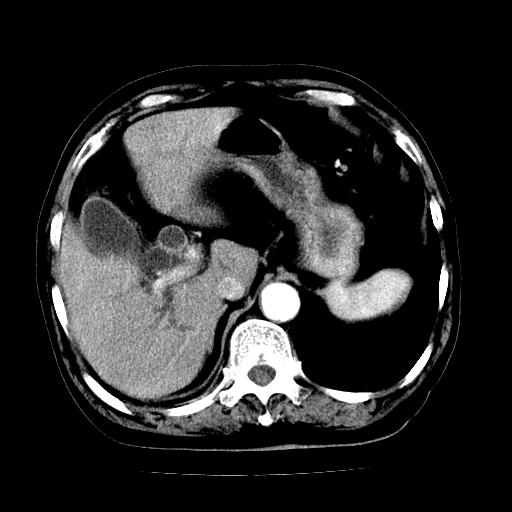

男,71岁,皮肤黄染四天。

肝内胆管,胆囊,肝总管级部分胆总扩大张

胆管癌并肝内外胆管扩张。

支持考虑胆总管癌并肝内外胆管扩张。 局部应薄扫。心包钙化。

胰腺上端胆总管内见软组织影,强化不明显,结合临床,还是考虑低位梗阻性黄疸,胆总管癌可能性大